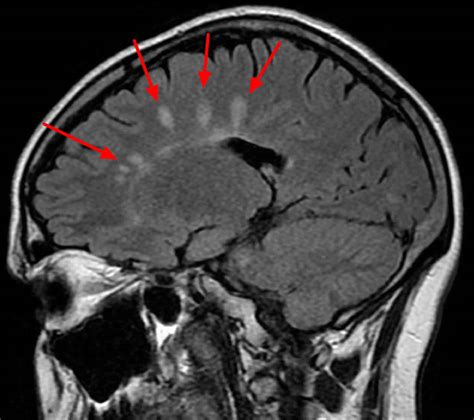

ms cause brain damage. There are some references to ms cause brain damage in this article. If you are looking for ms cause brain damage you've came to the right place. We have posts about ms cause brain damage. You can check it out below.